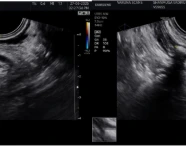

Postpartum Haemorrhage: A Case Series Highlighting Diverse Clinical Profiles and Evolving Management Strategies in a Tertiary Care Setting